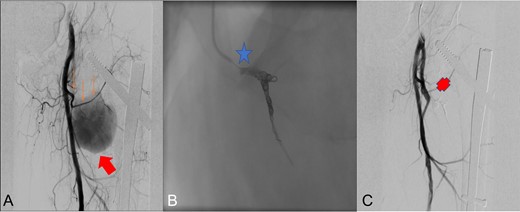

Radioescopic images sequence of the interventional procedure of embolization by retrograde right femoral puncture. A: Lateral femoral circumflex artery (thin arrows) branch of the deep femoral artery, pseudoanerysm (wide arrow). B: Embolization using two Axium 3D distal coils (star). C: Final result with embolized lateral circumflex artery (Cross).

The procedure achieved complete closure of the pseudoaneurysm and the vascular leakage was completely resolved stopping the active arterial bleeding, with permeability of the deep femoral artery (Fig. 3). The patient left the hospital 24 hours after procedure.